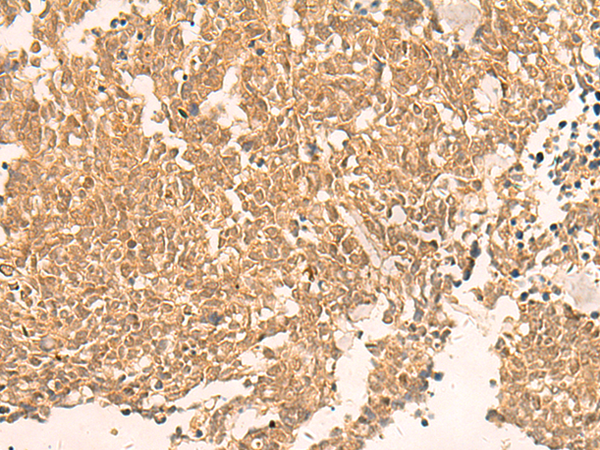

IHC positive control: |

Human ovarian cancer and Human lung cancer |